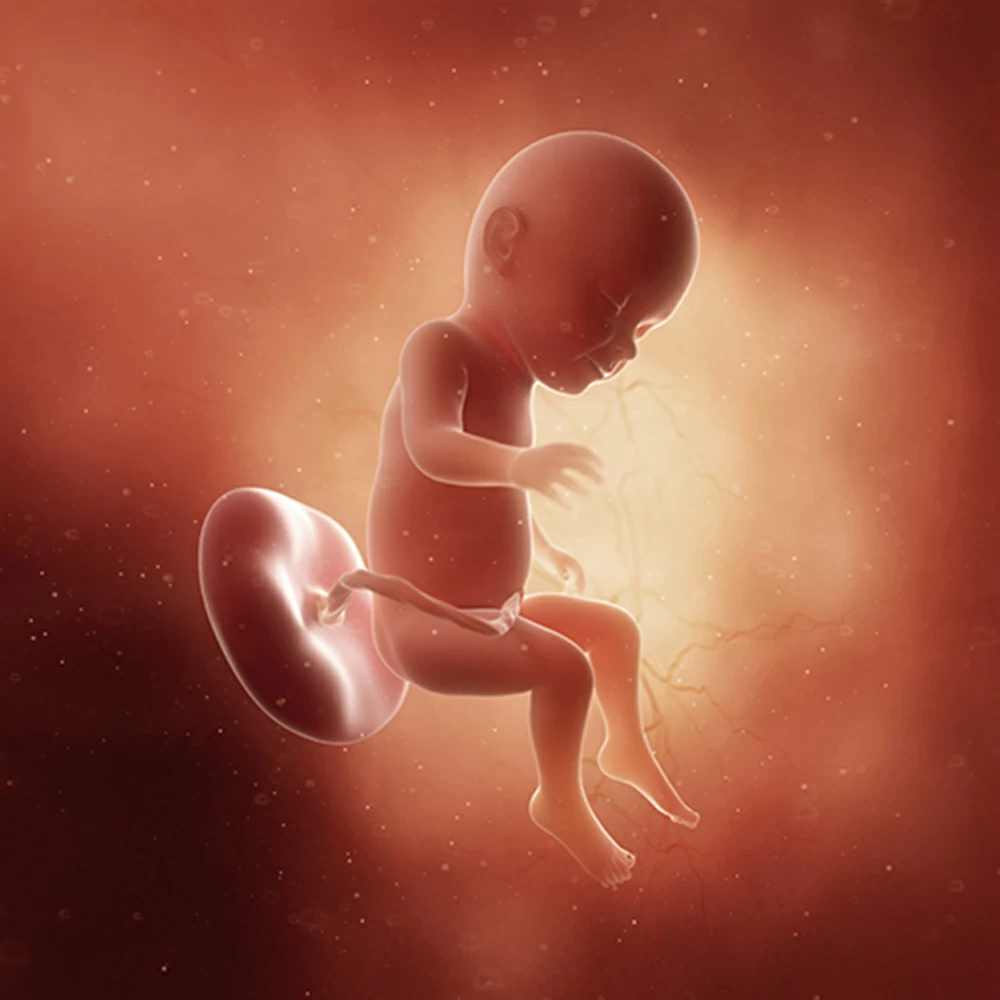

Тело плода остается непропорциональным: мелкое туловище, большие размеры головы, длинные руки и короткие ноги, согнутые во всех суставах и прижатые к животу.

Копчиково-теменной размер плода составляет около 10 см, вес плода – 70-75 грамм. Голова по-прежнему остается достаточно большой, но рост рук, ног и туловища начинает ее опережать.

Вес плода увеличивается до 100 грамм, копчиково-теменной размер – до 12 см.

К концу шестнадцатой недели плод уже полностью сформирован, у него есть все органы и системы. Активно работают почки, каждый час в околоплодные воды выделяется небольшое количество мочи.Кожа плода очень тонкая, подкожная жировая клетчатка практически отсутствует, поэтому через кожу просвечивают кровеносные сосуды. Кожа выглядит ярко-красной, покрыта пушковыми волосками и смазкой. Хорошо выражены брови и ресницы. Сформированы ногти, но они покрывают только край ногтевой фаланги.Формируются мимические мышцы, и плод начинает «гримасничать»: наблюдаются нахмуривание бровей, подобие улыбки.

На 22 неделе размеры плода увеличиваются до 28 см, вес – до 450-500 грамм. Размеры головки становятся пропорциональны туловищу и конечностям. Ноги практически все время находятся в согнутом состоянии.